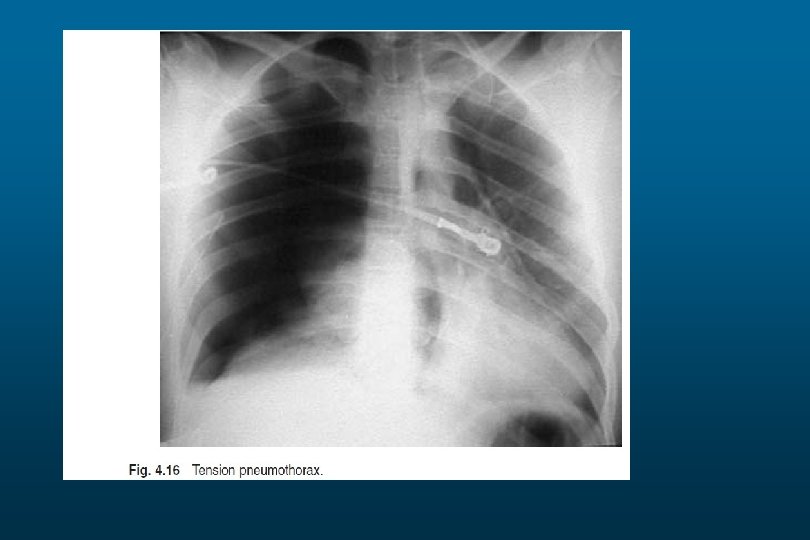

Pneumothorax